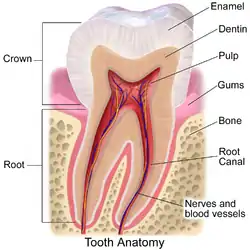

The alveolar process (/ælˈviːələr, ˌælviˈoʊlər, ˈælviələr/)[1] or alveolar bone is the thickened ridge of bone that contains the tooth sockets on the jaw bones (in humans, the maxilla and the mandible).[2] The structures are covered by gums as part of the oral cavity.

On the maxilla, the alveolar process is a ridge on the inferior surface, making up the thickest part of the bone. On the mandible it is a ridge on the superior surface. The structures hold the teeth and are encased by gums as part of the oral cavity.[11] Congruent with much of the mandibular canal, the alveolar process comprises cells, nerves, blood vessels, lymphatic vessels, and periosteum.[8] The alveolar crest terminates uniformly at about the neck of the teeth (within about 1 to 2 mm in a healthy specimen).[12][13]

The alveolar process proper encases the tooth sockets, and contains a lining of compact bone around the roots of the teeth, called the lamina dura.[8] This is attached by the periodontal ligament (PDL) to the root cementum.[8] Although the alveolar process is composed of compact bone, it may be called the cribriform plate because it contains numerous holes where Volkmann's canals pass from the alveolar bone into the PDL. The alveolar bone proper is also called bundle bone because Sharpey's fibres, part of the PDL, are inserted there. Sharpey's fibres in alveolar bone proper are inserted at a right angle (just as with the cemental surface); they are fewer in number, but thicker in diameter than those found in cementum.[8]

In the oral cavity, the alveolar processes are covered by gums. How the roots of the teeth, gums, and alveolar bone are related

How the roots of the teeth, gums, and alveolar bone are related Eroded alveolar process of the archaic human Homo heidelbergensis